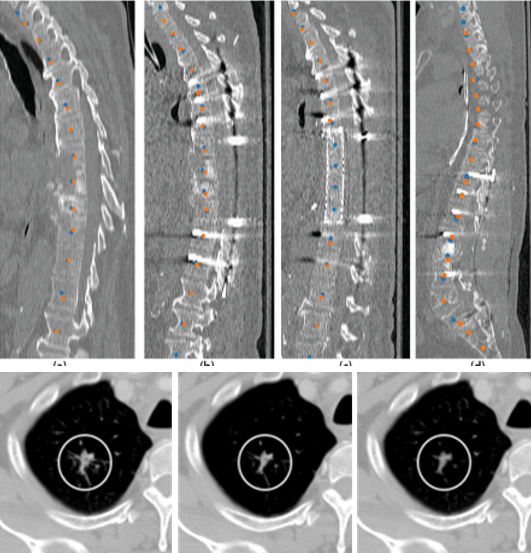

Vertebrae identification and localization

Chen Y, Gao Y, Li K, Zhao L, and Zhao J. Vertebrae identification and

localization utilizing fully convolutional networks and a hidden Markov model.

IEEE Transactions on Medical Imaging, 2020, 39(2): 387-399.